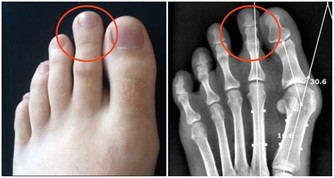

事實上,脂肪肝會導致更嚴重並且常常是致命的肝臟疾病,包括肝癌。肝病的主要階段包括單純性脂肪肝(脂肪變性)、纖維化和最嚴重的階段,也就是肝硬化,它可以導致肝功能衰竭和肝癌。